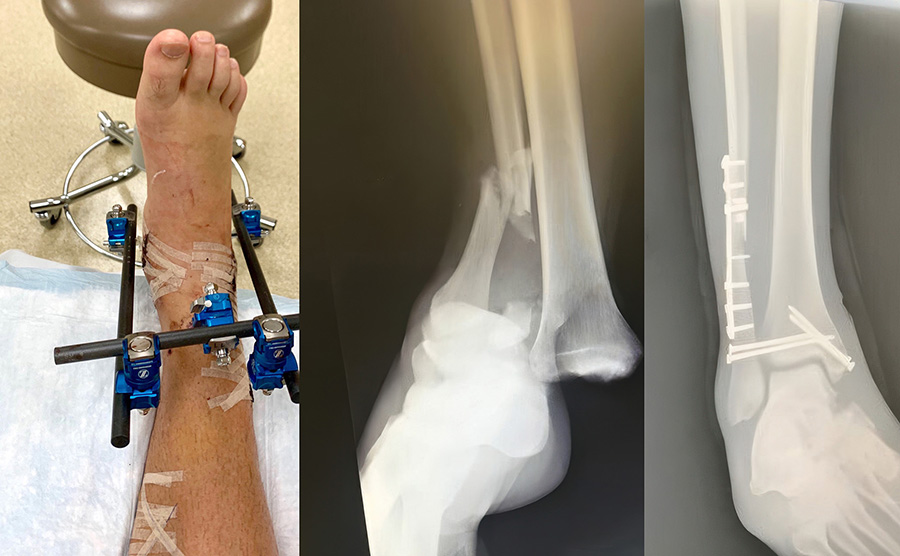

In July 2018, Abani was mountain biking with his son at Stevens Pass, WA when a split-second miscalculation sent him crashing into the mountainside. He suffered a severe compound fracture—breaking both his tibia and fibula—and began a long road to recovery. After initial surgery, rehab was slow and painful, and the question hung in the air: Would he ever return to the life he loved?

After a second surgery and a referral to Dr. Steven Benirschke at Harborview Medical Center, Abani was introduced to a new possibility: the Re-Aktiv™ brace with dynamic carbon spring support.